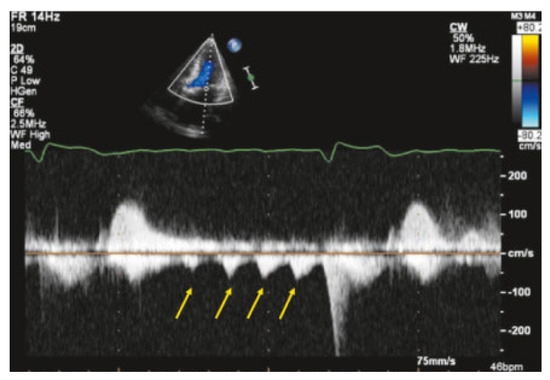

Value of Echocardiography in Differentiation of Acute Dyspnoea

by Ioannis Kapos and Felix C. Tanner

Echocardiography is one of the most effective imaging modalities for investigation of patients with acute dyspnoea. This review summarises appropriateness criteria and current guidelines for the use of cardiac ultrasound in common clinical scenarios presenting with acute dyspnoea, and illustrates such scenarios with [...] Read more.

Echocardiography is one of the most effective imaging modalities for investigation of patients with acute dyspnoea. This review summarises appropriateness criteria and current guidelines for the use of cardiac ultrasound in common clinical scenarios presenting with acute dyspnoea, and illustrates such scenarios with typical echocardiographic findings. Full article